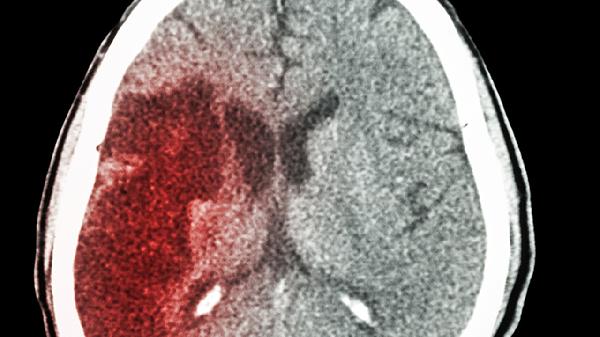

脑出血死亡的症状主要有剧烈头痛、喷射性呕吐、意识障碍、瞳孔异常以及呼吸心跳骤停。脑出血是指非外伤性脑实质内血管破裂引起的出血,病情凶险,致死率高,需立即就医。

患者可能迅速出现嗜睡、昏睡直至深度昏迷。意识障碍程度与出血量及部位相关,脑干出血者可在数分钟内陷入昏迷。部分患者会出现躁动、谵妄等精神症状,随后转为意识丧失,提示脑功能严重受损。

表现为双侧瞳孔不等大、对光反射迟钝或消失。脑疝形成时,病灶侧瞳孔先缩小后散大,最终双侧瞳孔固定散大。瞳孔变化反映脑干受压情况,是判断预后的重要指标,需紧急降颅压处理。

脑干生命中枢受压会导致呼吸节律紊乱,出现潮式呼吸、叹息样呼吸等异常模式,最终呼吸停止。随后出现心律失常、血压骤降直至心跳停止。此阶段已属临床死亡,即使复苏成功也常遗留不可逆脑损伤。